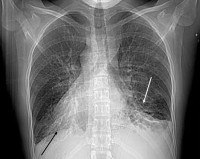

• Лучевая диагностика. На рентгенограмме грудной клетки наблюдаются правостороннее расположение тени сердца, зеркальная транспозиция лёгких. При исследовании назальных синусов часто выявляется недоразвитие фронтальных пазух. Компьютерная томография грудной полости помогает уточнить локализацию и распространённость бронхоэктазий.